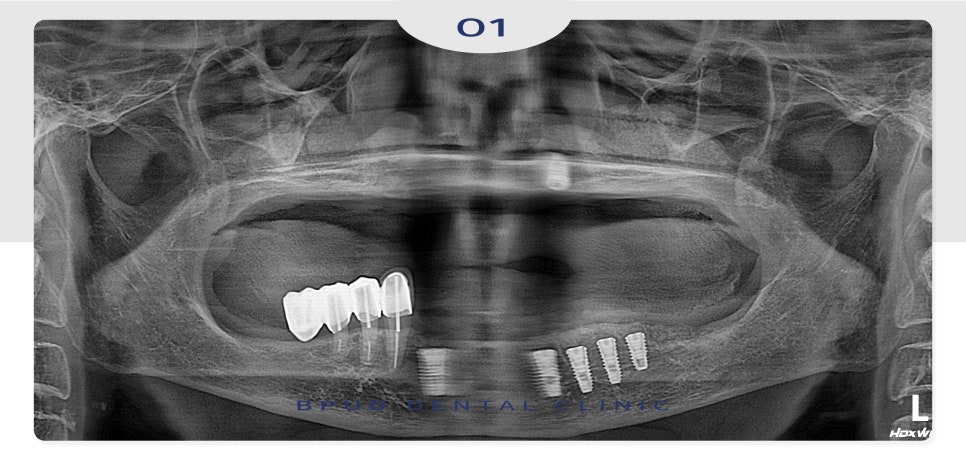

아래쪽은 흔들림이 심했던 치아들을

발치하고 살릴 수 있는 치아들은 살린 뒤

어금니 부위를 연결한 캔틸레버 브릿지

형태로 마무리를 하였는데요.

아래쪽의 경우에는 발치 후 즉시 식립

진행 후 위쪽 임플란트를 제거하고

뼈이식을 동시에 시행하였습니다.

약 4~5개월 후 위쪽 임플란트도

식립을 진행하였습니다.

식립 4-5개월 후 최종 보철까지

완성하였는데요.